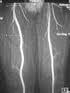

Ablavar has an MRA indication to evaluate aortoiliac occlusive disease.

In Phase 3 clinical studies, Ablavar, the contrast agent that Lantheus Medical Imaging launched today, demonstrated statistically greater sensitivity (detecting disease when present) compared with noncontrast MRA[ii]. These studies, which supported the U.S. Food and Drug Administration (FDA) approval of Ablavar, show that MRA images using Ablavar provided diagnostic accuracy comparable to conventional X-ray angiography,[iii],[iv] an invasive procedure which involves insertion of a catheter into the arteries in the upper thigh (groin area) or arm[v].

“Ablavar provides distinct advantages over X-ray angiography, the current standard of care in diagnosing AIOD,” said Mark G. Hibberd, M.D., Ph.D., senior medical director, Global Medical Affairs, Lantheus Medical Imaging, Inc. “Ablavar provides high resolution images comparable to conventional X-ray angiography (the current gold standard), which offers radiologists a clear, enhanced visualization of patients’ arteries. However, Ablavar is given in a single, low dose injection, does not require catheter insertion into a patient’s arteries, and does not expose patients to ionizing radiation, all of which are tangible benefits to patients.”